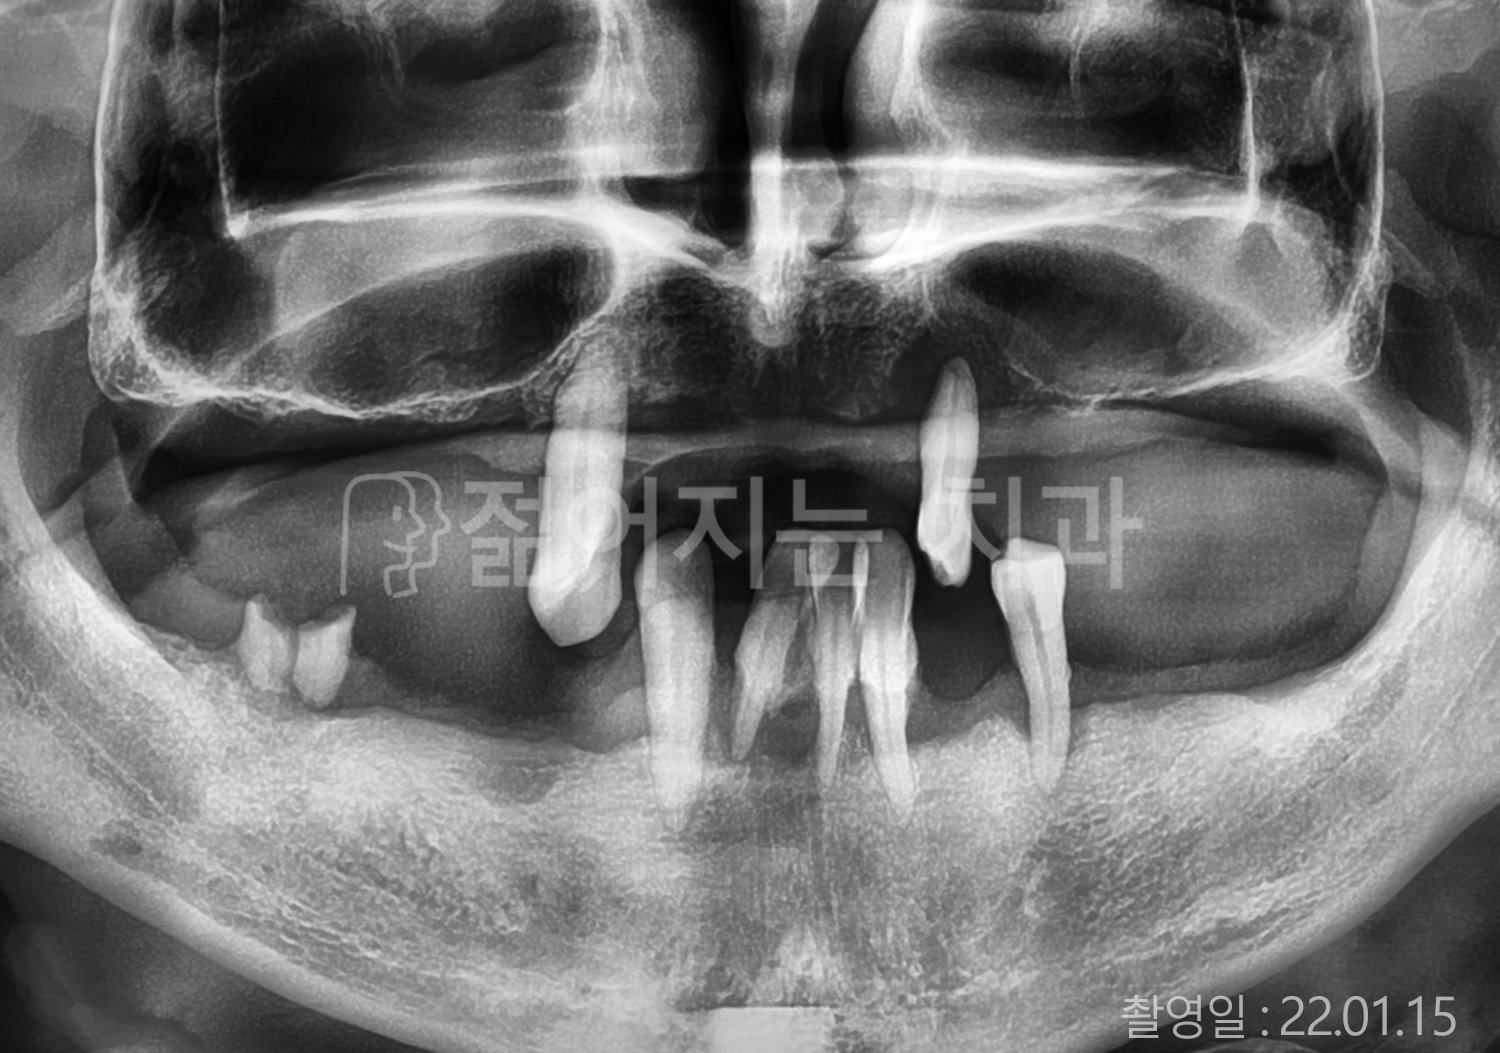

• 70대 고혈압, 당뇨 전체치아 10개 이상 임플란트

• 50대 고혈압, 당뇨 전체치아 10개 이상 임플란트

• 60대 고혈압, 당뇨 전체치아 10개 이상 임플란트

• 50대 전체치아 10개 이상 임플란트

• 70대 당뇨 전체치아 10개 이상 임플란트

• 80대 전체치아 10개 이상 임플란트

• 40대 전체치아 10개 이상 임플란트

• 60대 고협압, 고지혈증 전체치아 10개 이상 임플란트

• 60대 전체치아 10개 이상 임플란트